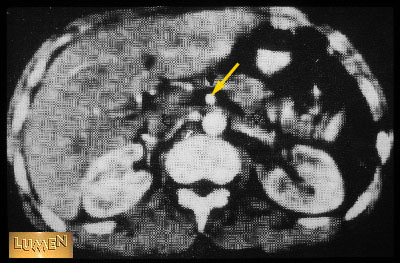

Question: Identify.

Answer

Superior mesenteric artery.